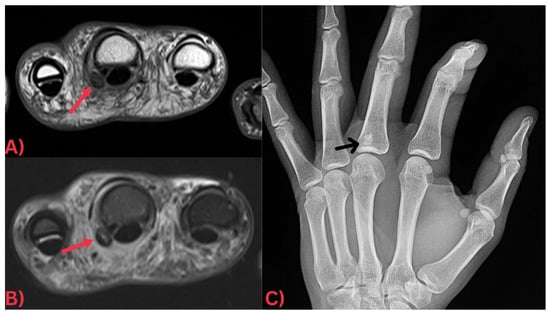

Specifically, MRI images display hydroxyapatite deposits as regions with low signal intensity across both T1- and T2-weighted images, attributable to the high mineral content of hydroxyapatite, a form of calcium phosphate crystals [27]. Consequently, this results in its manifestation in MRI images (Figure 3). Concurrently, MRI also reveals inflammation signs within surrounding soft tissues, such as edema and increased signal intensity on T2-weighted images [28] (Figure 4). Edema, a common response to inflammation or injury, indicates the body’s reparative efforts, while a heightened signal intensity on T2-weighted images typifies inflammation and is present in several conditions, including HADD (Figure 5).

Figure 4. (A) Axial PD and (B) axial T2 fat-saturated MRI images of the hand demonstrating a well-defined globular low signal intensity focus at the volar capsule of the metacarpophalangeal joint of the middle finger (red arrows) with significant surrounding soft tissue edema. Note how this focus is more easily discernable on the (C) X-ray image of the hand, which clearly demonstrates that it is a focus of calcification (black arrow).